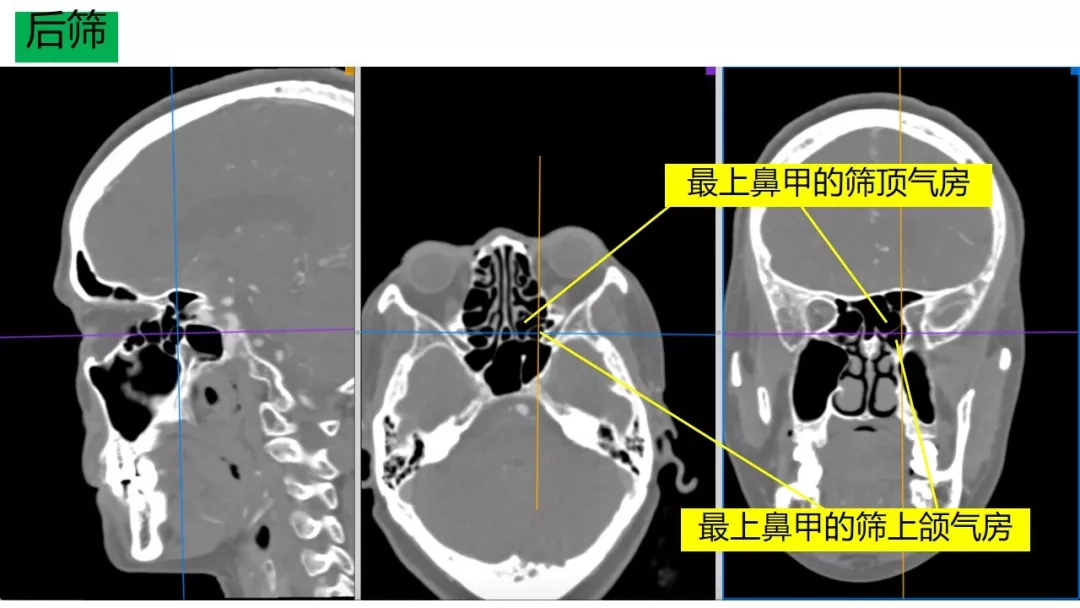

Osirix冠矢轴